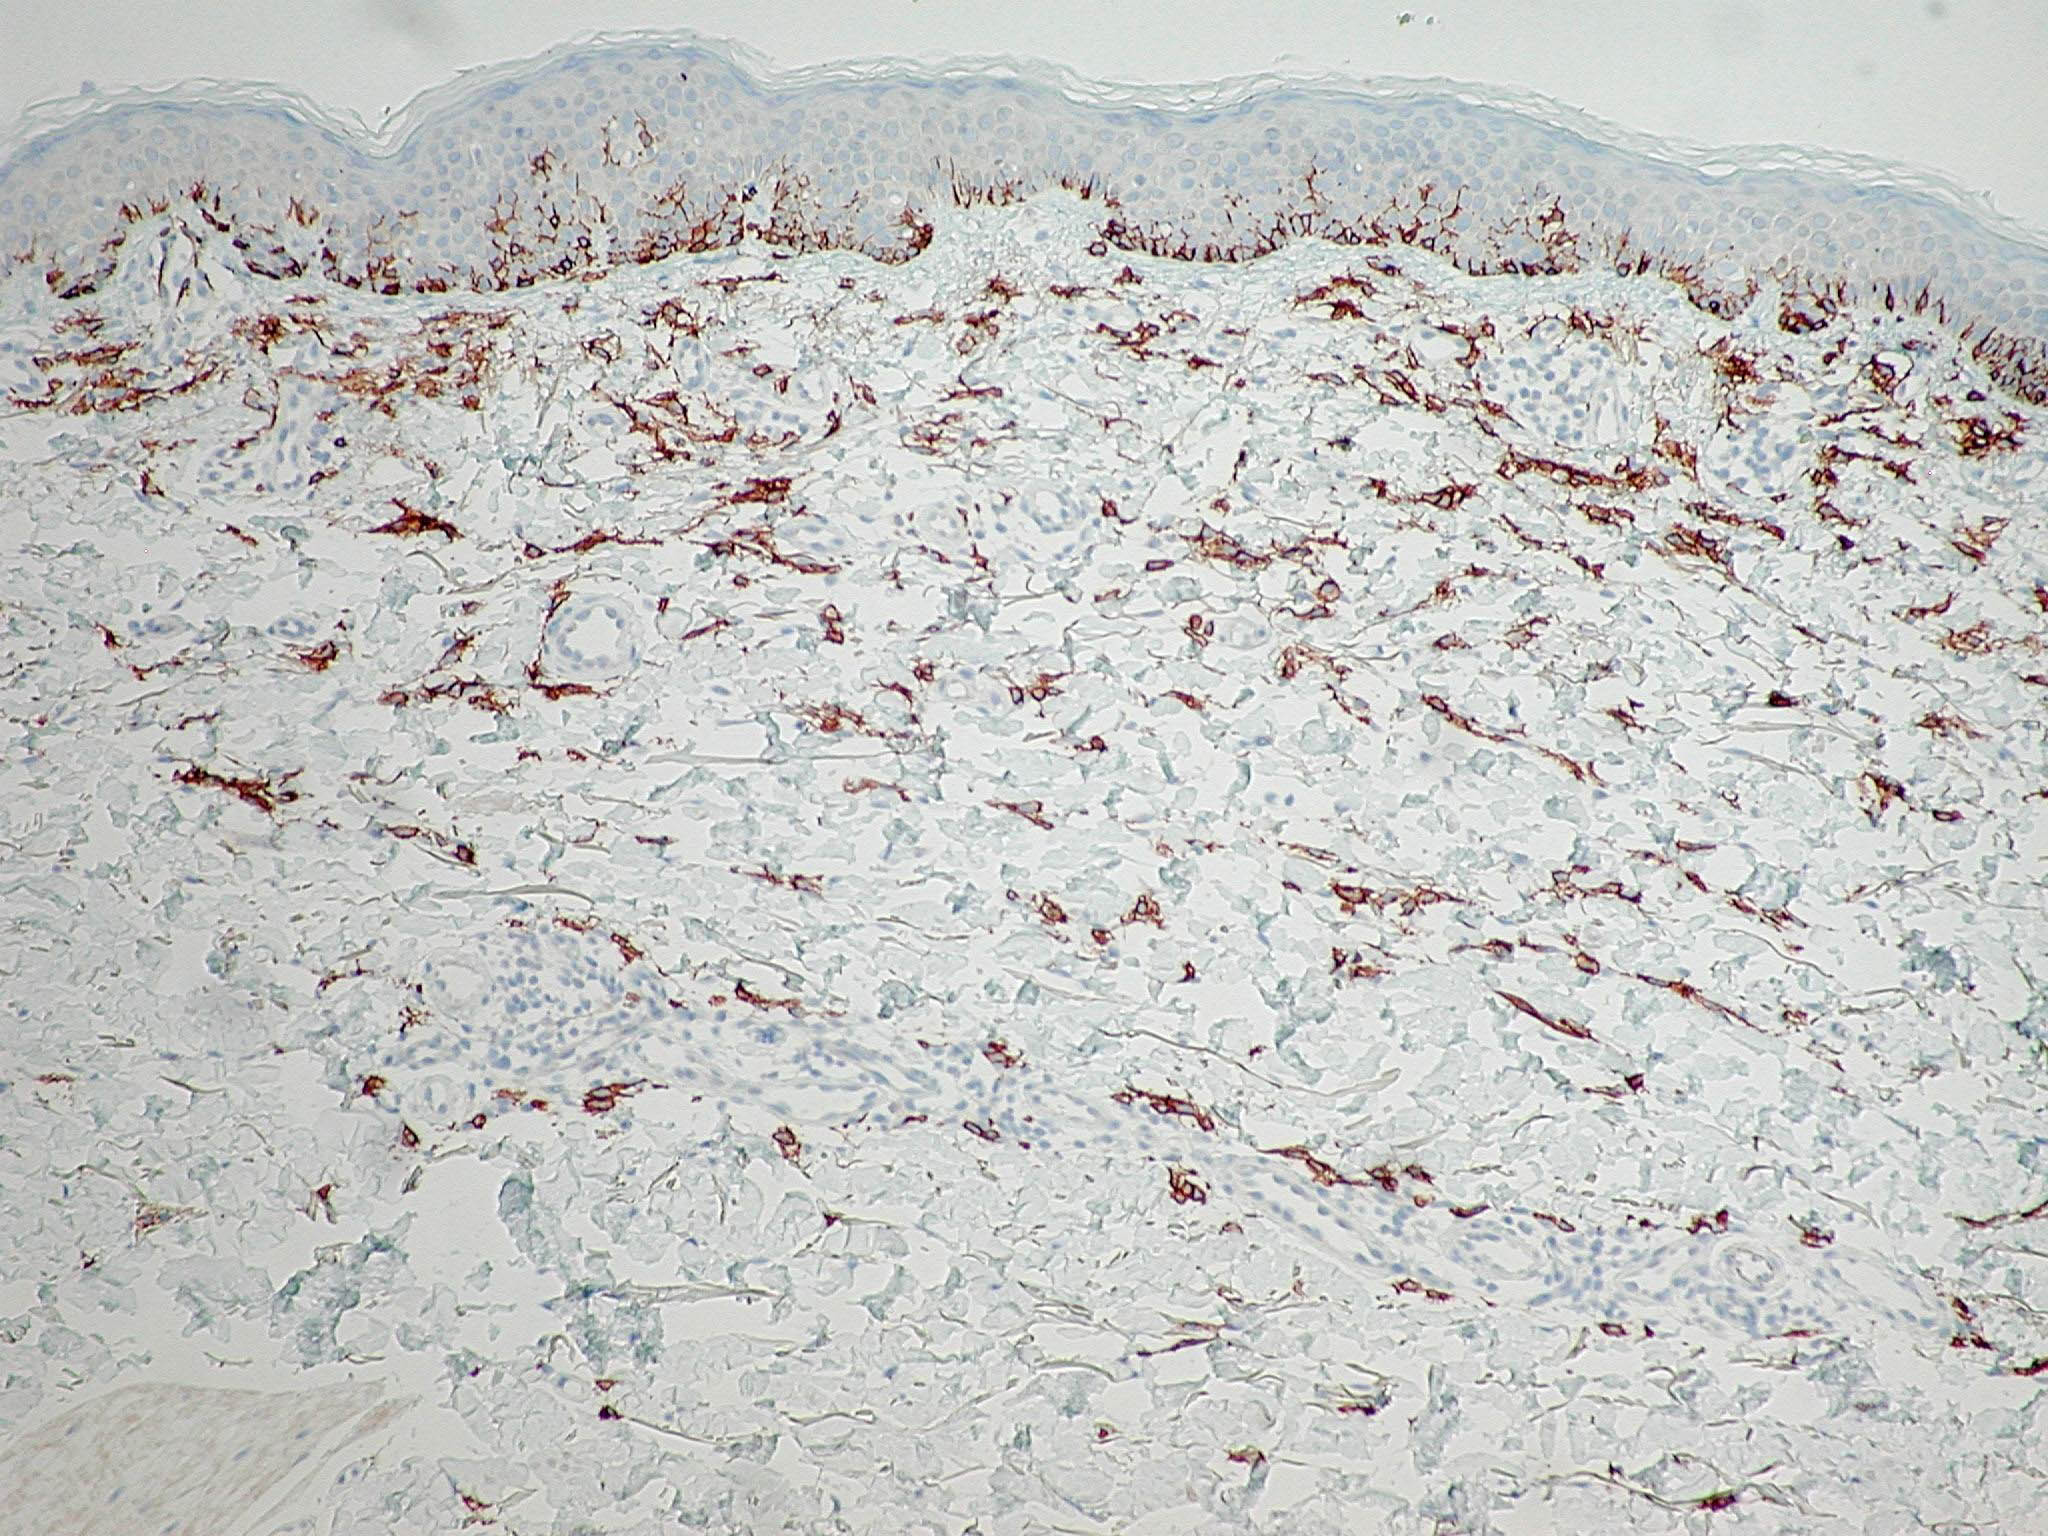

mastocytose